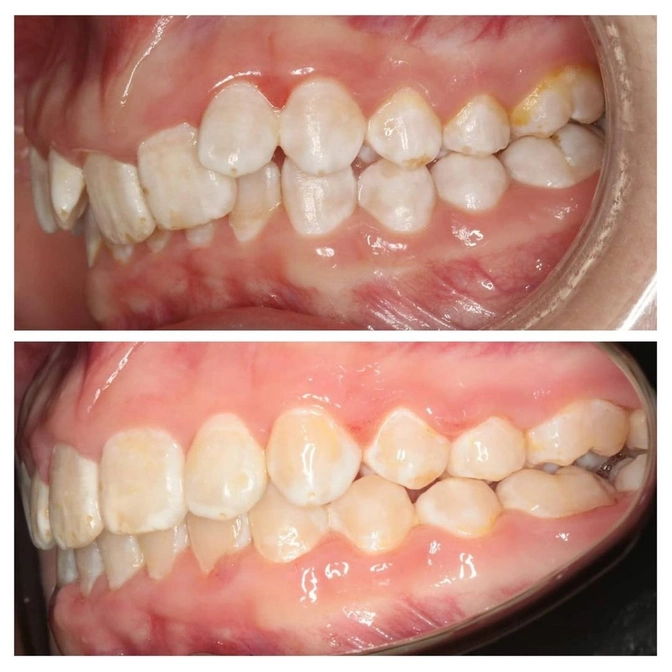

Исправление прикуса: результат за год.

Отличную работу провела наш ортодонт Диана Кива.

Пациент все указания врача выполнял точно и вовремя, благодаря этому время лечения сократилось почти в 2 раза!

Ровно 1 год потребовался, чтобы исправить прикус и положение зубов.

Но вы уже наверняка обратили внимание на "пятнистые" зубы.

Это поражение называется флюороз.

Такой порок развития возникает ДО ПРОРЕЗЫВАНИЯ зубов при длительном употреблении воды или продуктов с повышенным содержанием фтора.

До сих пор многие ортодонты не берутся исправлять прикус, если зубы поражены флюорозом.

Всё потому, что брекеты якобы отклеиваются от измененной эмали.

Но технологии не стоят на месте!

В современных стоматологиях при должном уровне профессионализма ортодонты не боятся лечить таких пациентов.

Доктор Кива справилась отлично!

В процессе лечения этого пациента у него не отклеился ни один брекет и состояние эмали совершенно не ухудшилось.